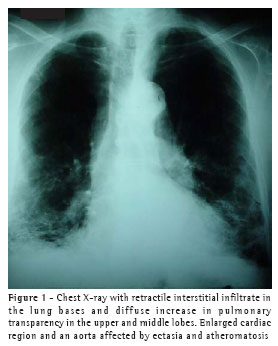

A high-resolution computed tomography scan of the chest (Figure 2) revealed the presence of retractile reticular interstitial infiltrate in the lower lobes, as well as thickening of the interlobular septa accompanied by an evident calcium component to the left, centrilobular emphysema in the upper lobes, left pleural thickening, an aorta affected by ectasia/atheromatosis, and normal cardiac region.